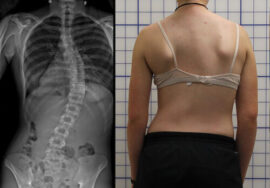

العلاقة بين الكتفين غير المتوازنين والجنف (اعوجاج العمود الفقري)

أحد أبرز الأسباب وراء عدم توازن الكتفين هو الجنف، وهو انحناء جانبي غير طبيعي في العمود الفقري. هذا الانحناء يجعل الجسم يميل لأحد الجانبين، مما يؤدي إلى:

رفع أحد الكتفين.

بروز أحد لوحي الكتف.

خلل في التوازن العام للجسم.

في حالة الجنف عند المراهقين، قد يكون عدم توازن الكتفين هو العلامة الأولى التي يلاحظها الأهل أو المعلمون، لذلك من المهم عدم تجاهل هذا العرض.

كيف يتم التشخيص؟

يعتمد تشخيص السبب على الفحص السريري وأحيانًا التصوير بالأشعة. يشمل التشخيص:

فحص وقوف الطفل أو المراهق ومراقبة الكتفين والظهر.

اختبار الانحناء للأمام لملاحظة أي بروز أو عدم توازن.

أشعة سينية (X-Ray) لتحديد ما إذا كان هناك انحناء في العمود الفقري (زاوية كوب).